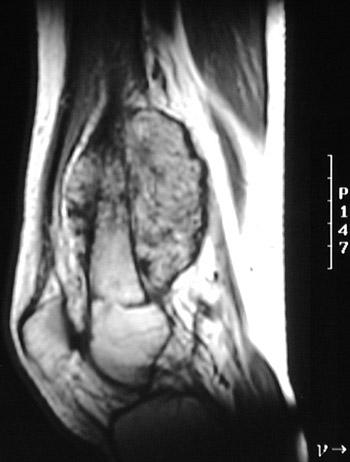

MRI scans of an osteosarcoma of the distal femur are seen here (above: axial T2 weighted FSE with fat saturation, below: sagittal T1 weighted FSEIR). There is extensive

cortical disruption

.